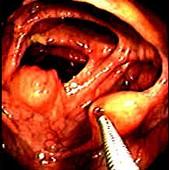

问题 女性,60岁,无临床症状,查体无明显异常,体检时的结肠镜检查图片(图1、2),2年后复查肠镜图片(图3、4),此患者最可能的诊断是 ( )

选项 A.Crhon病 B.大肠癌 C.脂肪瘤 D.大肠息肉 E.溃疡性结肠炎

答案 C